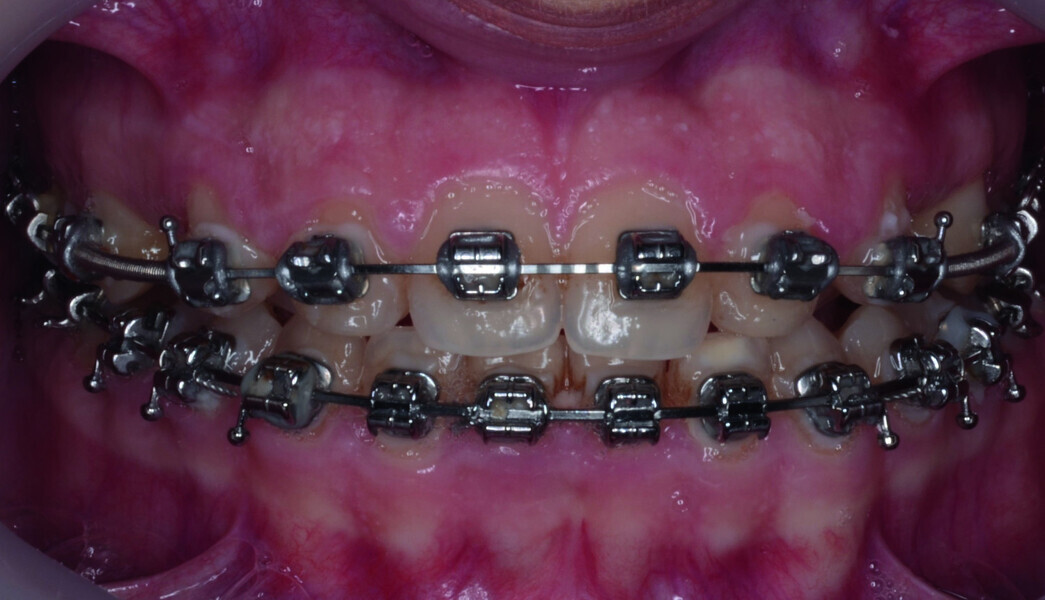

Orthodontic management of maxillary lateral incisors agenesis